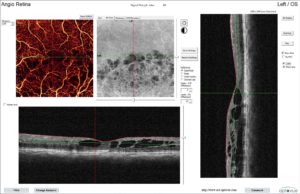

AngioVue Essential offers high-resolution, noninvasive imaging of retinal vasculature to assist clinicians to visualize ocular disease, the company said in a press release. The new feature that is OCT-A supplies a report that displays OCT B-scans and layers of a cortical vasculature. The system gives the accession of ocular health screening. It’s designed particularly for practices to permit adoption of OCT-A and OCT to the workflow with minimum disruption.

Optovue’s AngioVue Retina provides retinal experts with the ability to quickly visualize the existence or absence of retinal vessels and assess new information concerning the microvasculature in detail.

Angiovue makes it possible for clinicians to image the motion of scattering particles like erythrocytes (red blood cells) using sequential OCT cross-sectional scans that are replicated in the same location on the retina. Capturing the dynamic movement of the erythrocytes (red blood cells) allows a 3D visualization of the perfused vasculature and microvasculature of the retina. Unlike Angiovue permits visualization of vasculature within specific layers of the retina, without the effects of pooling or discoloration.

- Designed for Visualization Even in the Choroid AngioVue’s Outer Retinal Zone is a single en face slab that visualizes a wide spectrum of pathologies arising from abnormal vessel growth in the retinal-choroidal interface, such as Type 1 and 2 CNV. The AngioVue Imaging System utilizes a proprietary projection artifact removal technique resulting in unparalleled image quality uniquely suited for enhanced neovascularization visualization.

- Exclusive Technology The AngioVue Imaging System uses the proprietary SSADA algorithm to produce stunningly detailed images and to minimize scan acquisition time. Optovue’s exclusive Motion Correction Technology (MCT™) reduces motion artifact to give you detailed images that increase your diagnostic confidence.